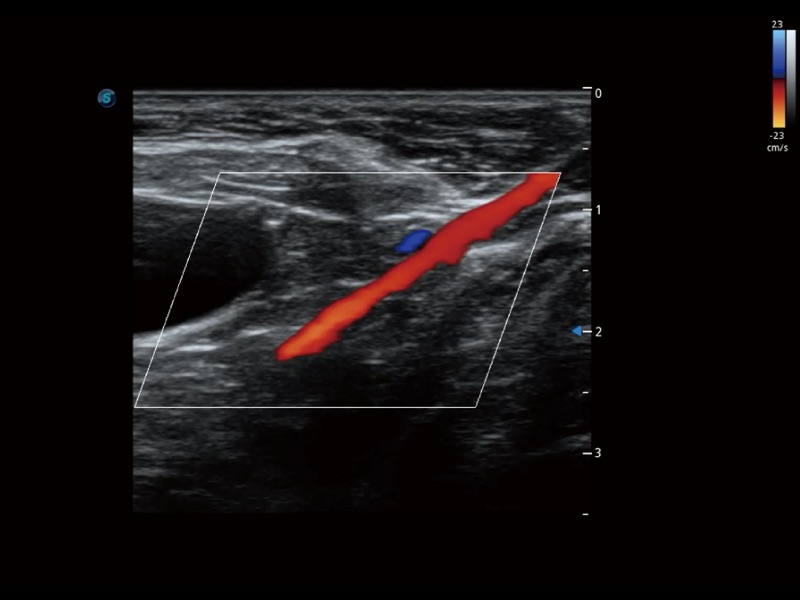

• 宽景成像

通过色彩血流和实时宽景相结合,可观察到完整的静脉或动脉的血流,方便医生检查。实时扫查过程中,如有任何操作失误也可以很容易地进行回扫擦除,而不会中断扫查。

(犬)左室长轴血流

(犬)髂动脉血流